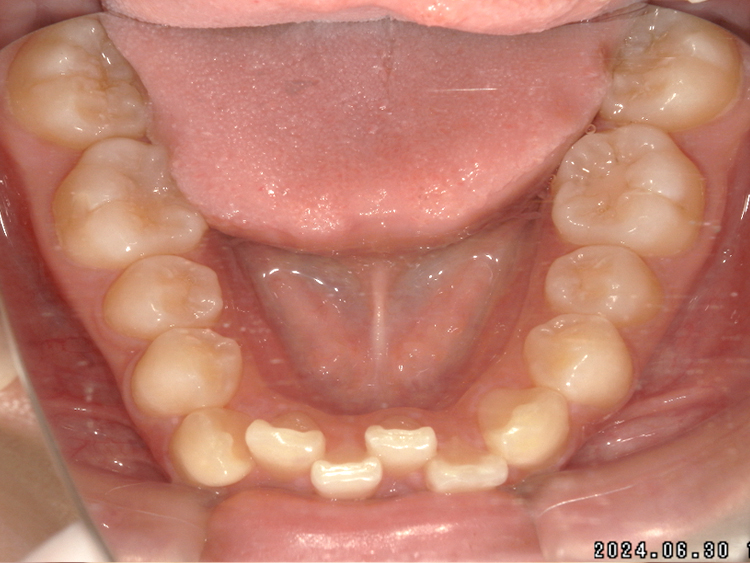

症例4

Before

After

| 主訴 | 上下前歯のがたつき |

|---|---|

| 年齢 | --- |

| 治療 期間 |

約9ヶ月 |

| 治療 内容 |

インビザラインiGoで上下顎の治療。 |

| 治療費 | ¥550,000(税込)/調整料含む |

| 治療のリスク | 矯正終了後は、リテーナーを指示通りに使用し、歯の後戻りを防ぐ必要があります。 |